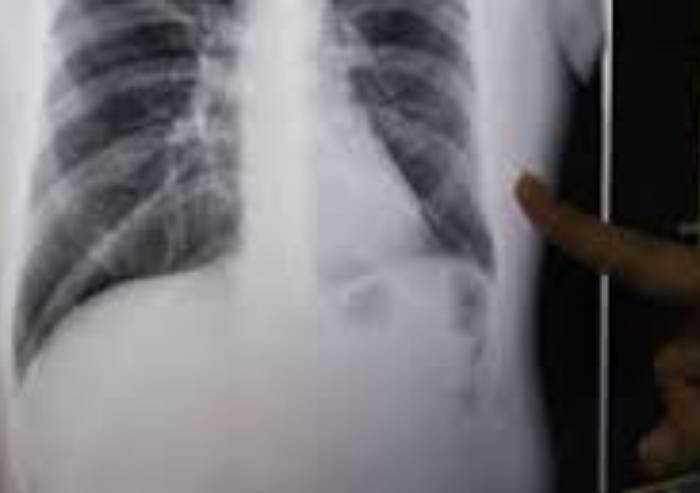

Un caso di tubercolosi (TBC) in un’ospite di una Casa residenza per anziani di Montefiorino è stato segnalato al Servizio igiene pubblica dell’Azienda USL di Modena.

Come previsto dai protocolli delle malattie infettive, l'Azienda USL ha immediatamente informato il personale della struttura, gli ospiti e i loro familiari, e, pur trattandosi di un caso a bassissima contagiosità, prudenzialmente sono state avviate tutte le procedure previste per l'individuazione dei contatti, lo svolgimento degli accertamenti necessari e la sorveglianza sanitaria dei contatti.

Attualmente la paziente è ricoverata presso il reparto di Malattie Infettive del Policlinico in buone condizioni